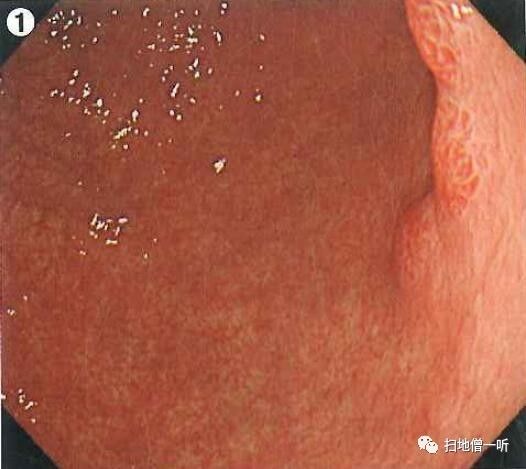

A2:息肉样病变在图3及图4

体上部大弯前壁可见发红息肉样隆起性病变,周围粘液较多,冲洗干净后需考虑与增生性息肉?胃癌?等鉴别。

边缘观察可见粘膜粗大,需考虑增生性息肉?顶部可见轻微凹陷,粘膜结构消失